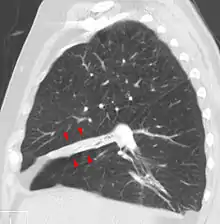

| Atelectasis of a person's right lung | |

Clinically significant atelectasis is generally visible on chest X-ray; findings can include lung opacification and/or loss of lung volume. Post-surgical atelectasis will be bibasal in pattern. Chest CT or bronchoscopy may be necessary if the cause of atelectasis is not clinically apparent. Direct signs of atelectasis include displacement of interlobar fissures and mobile structures within the thorax, overinflation of the unaffected ipsilateral lobe or contralateral lung, and opacification of the collapsed lobe.In addition to clinically significant findings on chest X-rays, patients may present with indirect signs and symptoms such as elevation of the diaphragm, shifting of the trachea, heart and mediastinum; displacement of the hilus and shifting granulomas.[9]